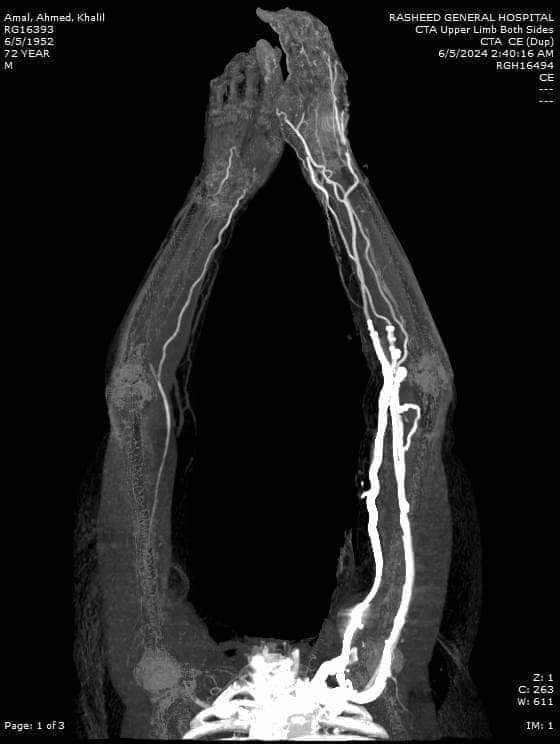

نجح الفريق الطبي بمستشفى رشيد المركزى للمرة الثالثة في اجراء عملية جراحية متقدمة حيث قام الفريق الطبي بقسم الجراحة بإجراء عملية جراحية لتسليك شريان ذراع أحد السيدات واستئصال الجلطات من الذراع الأيمن لمريضة بالعناية المركزه وتم إنقاذ الذراع من البتر ، والمريضه في قسم العناية المركزة بحالة مستقرة .

وقام بإجراء العملية الجراحية بنجاح أعضاء الفريق الطبي الآتى أسماؤهم "الدكتور منير الفخراني استشاري الأوعية الدموية، الدكتور محمد المحلي أخصائي الجراحة، الدكتور السيد عمران أخصائي التخدير ، والدكتور محمد زاهر أخصائي العناية المركزة ونائب مدير المستشفى ، الدكتور أحمد الترمسى رئيس قسم العناية ، ومشرفات تمريض قسم الجراحة والعمليات ، والعناية المركزة ، وقسم الأشعة .